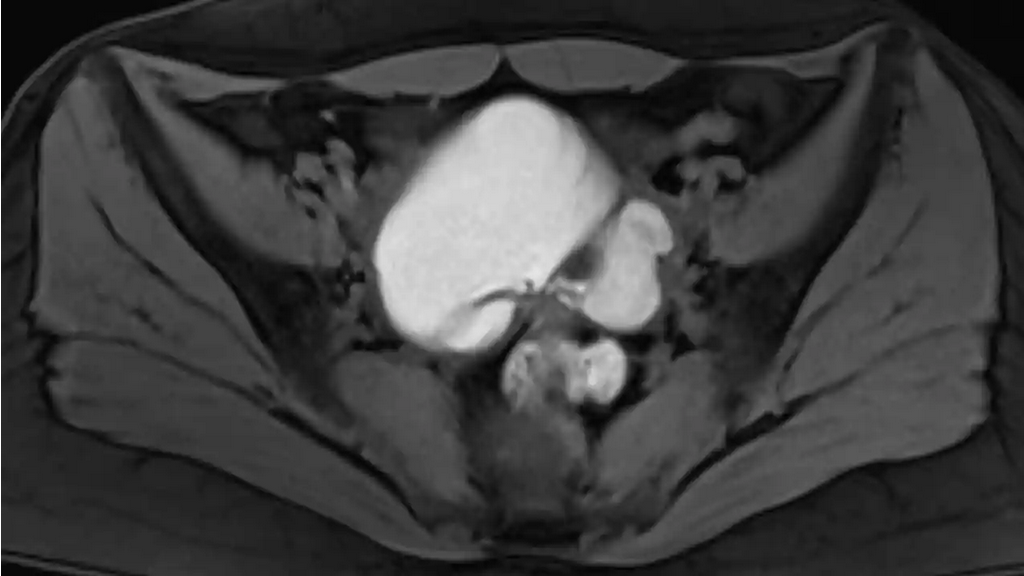

Se trata de un tipo de cáncer de ovario, el que afecta a mujeres con mutaciones BRCA 1 y 2, y que supone el 22% de los carcinomas de ovario.

Este tipo de tumor es de los más agresivos y el quinto que más mortalidad produce en las mujeres, detrás del cáncer de mama, el colorrectal, el de páncreas y de pulmón.

Los resultados de los ensayos de fase III SOLO-1 y PAOLA-1, presentados por el profesor Jonathan Ledermann, del UCL Cancer Institute, de Londres, muestran los beneficios de supervivencia a largo plazo con un fármaco (olaparib) en pacientes con cáncer de ovario avanzado recién diagnosticado.